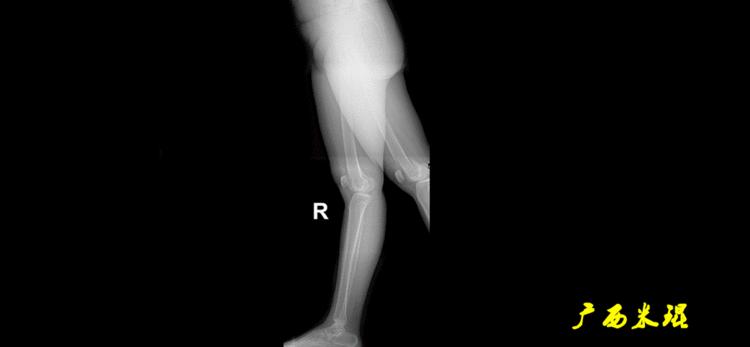

机械轴要分前后位及侧位,站立前后位(也就是冠状面)股骨头中心与踝关节中心的连线通过膝关节中心,这是下肢的机械轴线,也就是下肢力线,常说Mikulicz线。冠状面的力线评估在临床工作中最常用、最基础、最重要。

站立侧位(矢状面)股骨头中心与踝关节中心的连线也通过膝关节中心,这也是下肢的机械轴线,这也是下肢力线。

矢状面的下肢力线常常被医生忽视,其实它的改变也是膝关节疼痛的常见原因。